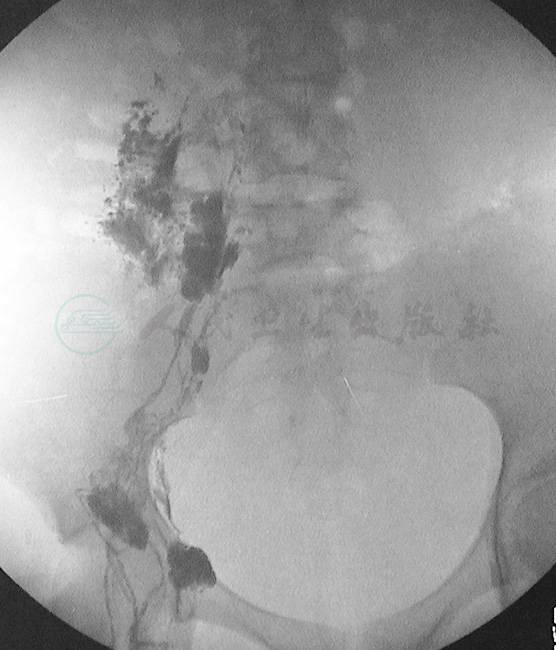

因此,乳糜性腹水可常伴有乳糜性胸水,也可伴有其他部位的乳糜性病变(图4)。

图4女性,58岁,全身核素淋巴显像显示右下肢淋巴水肿,乳糜腹水,左侧乳糜胸